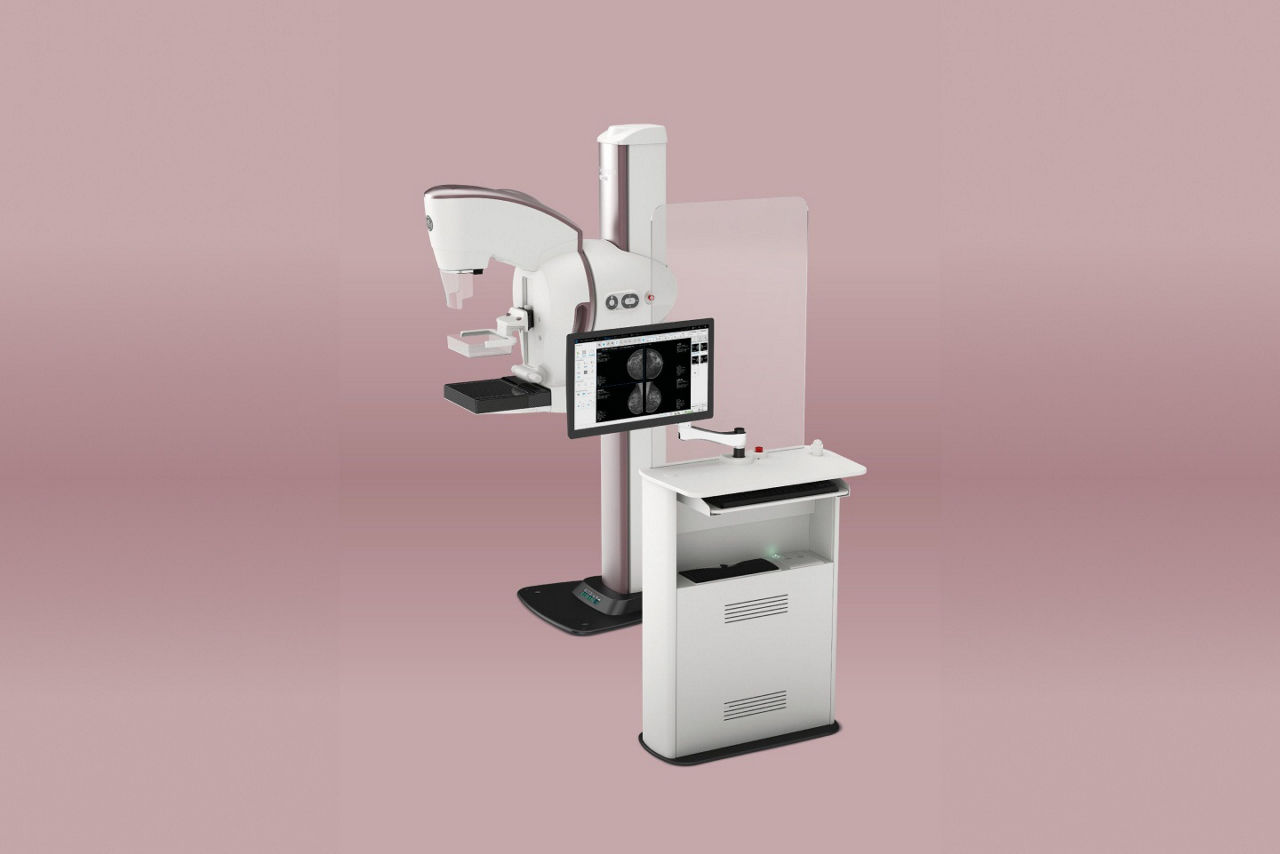

Premium technology empowerment

Benefit from GE HealthCare's world-class technology for enhanced patient care.

Optimized dose management

Automatic Optimization of Parameters (AOP) ensures precise dosing.

Customized image accessibility

eContrast post-processing offers four contrast levels for optimal diagnosis.